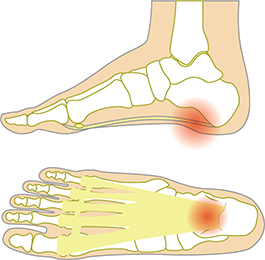

족저근막염은 외부 요인에 의해 갑자기 발생하는 것이 아니라 서서히 증상이 진행되는 것을 볼 수 있습니다. 발뒤꿈치 중앙보다 약간 앞으로 뻗어 있으므로 내측에서 발생하고, 아침에 일어나거나 오래 앉아 있다가 갑자기 일어날 때 강도가 높게 나타납니다. 잠을 자거나 앉는 것처럼 몸이 이완된 상태에서 움직이면 갑자기 늘어나 통증이 오게 됩니다.

통증은 일반적으로 발뒤꿈치 안쪽과 바닥에서 느껴집니다.

족저 근막염 증상으로 80%이상은 한쪽 발의 통증을 호소하고 있습니다. 대부분 사람들이 양쪽의 발을 사용하기보다 한쪽 발을 더 많이 사용하는 습관 때문입니다. 이유는 사람들의 양쪽 다리 길이가 다르며, 더 긴 쪽 다리의 발에 더 많은 압력이 가해지기 때문입니다. 그렇기에 한쪽 발 통증이 나타날 수 있습니다.

- 아침에 일어나서 몇발짝 걸었을 때 찌릿한 심한 통증을 느낀다.

- 발 뒤꿈치 안쪽의 심한 통증을 느낀다.

- 발 아치 중앙에 심한 통증이 있다.

- 앉았다 일어서면서 걷기 시작했을 때 발 뒤꿈치에 심한 통증을 느낀다.